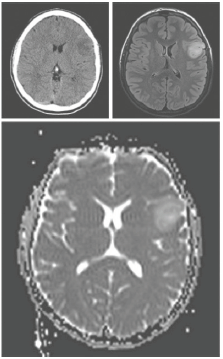

Um paciente de 41 anos de idade é admitido no

pronto-socorro com história de crise convulsiva

tônico-clônica generalizada. Foi submetido à

ressonância de crânio, como mostra a imagem a

seguir.

O método cirúrgico auxiliar mais apropriado para

esse caso é: